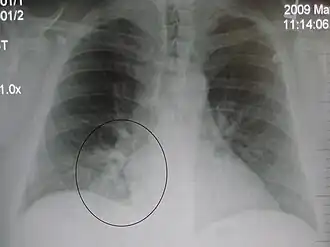

AP CXR showing left lower lobe pneumonia associated with a small left sided pleural effusion -

AP CXR showing right lower lobe pneumonia -

Left upper lobe pneumonia with a small pleural effusion.